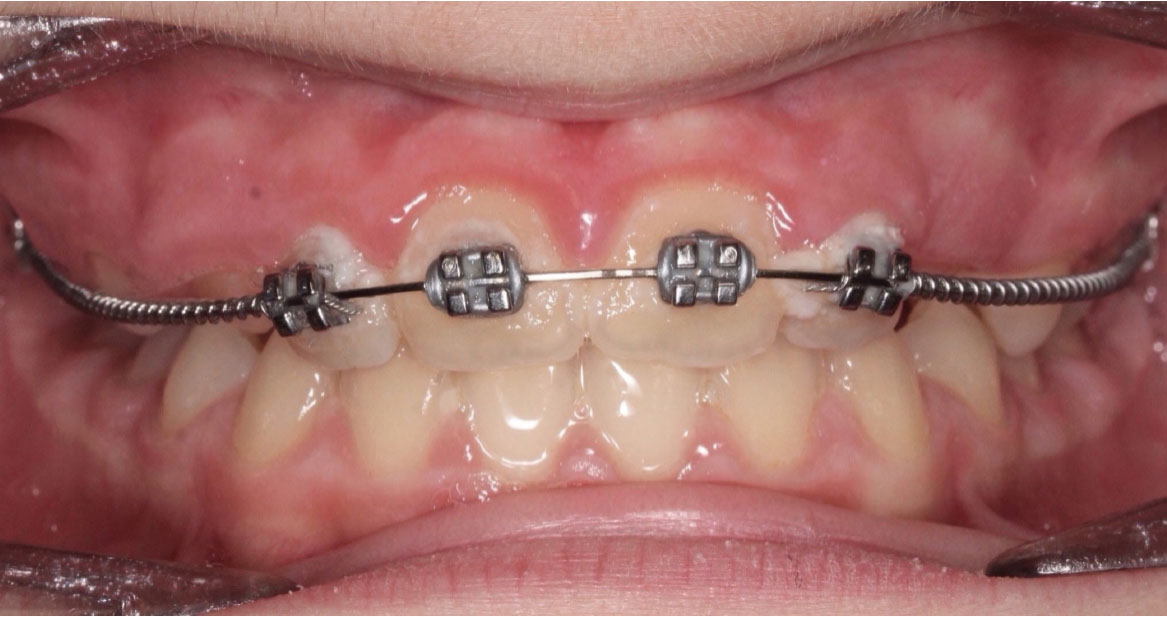

Bandaggio e sequenza archi

A tre mesi dalla cementazione dell’ERP si programma il bandaggio parziale superiore da 12 a 22 (Mini Master, prescrizione MBT, slot 22×28, American orthodontics) posizionando in maniera strategica i bk su 12 e 22, per il controllo del tip ed evitare interferenza con il tragitto eruttivo di 13 e 23. Sono state posizionate delle open coil attive e arco 016 Tanzo (fig. 8).

Fig. 8A Terapia intercettiva con REP e bandaggio parziale superiore.

Fig. 8B Terapia intercettiva con REP e bandaggio parziale superiore.